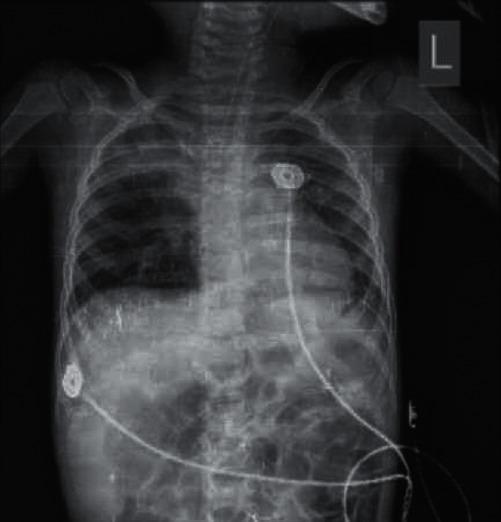

The manifestations of novel coronavirus are diverse and can manifest through respiratory, gastrointestinal, and even nervous symptoms. Respiratory involvement is usually an upper tract infection or pneumonia but can also present as other forms of pulmonary disorders. A 3-year-old boy presented with cough, hoarseness, and stridor. He was treated with dexamethasone and nebulized adrenaline and a clinical diagnosis of croup was established. After treatment, his symptoms improved for a short time, but suddenly cough exacerbated and was accompanied by respiratory failure and seizures. He was then intubated and mechanically ventilated. Because of the coronavirus epidemic, Reverse-Transcription Polymerase Chain Reaction (RT-PCR) assay was taken from the pharyngeal secretions and was positive. The child was isolated. Due to excessive respiratory secretions and worsening of the general condition, bronchoscopy was performed depicting an image compatible with bacterial tracheitis. He was treated with broad-spectrum antibiotics, antivirals, and supportive care. Finally, after 4 weeks of treatment, the child was discharged in good general condition. Croup is one of the respiratory symptoms of novel coronavirus and can be a risk factor for bacterial tracheitis. Therefore, the presence of clinical manifestations of croup indicates the need for coronavirus PCR testing.

新型冠状病毒的表现多种多样,可通过呼吸道、胃肠道甚至神经系统症状表现出来。呼吸道受累通常为上呼吸道感染或肺炎,但也可能表现为其他形式的肺部疾病。一名3岁男孩出现咳嗽、声音嘶哑和喘鸣。他接受了地塞米松和雾化肾上腺素治疗,并确诊为喉炎。治疗后,他的症状短期内有所改善,但突然咳嗽加剧,并伴有呼吸衰竭和癫痫发作。随后他被插管并进行机械通气。由于冠状病毒疫情,从咽部分泌物中进行了逆转录聚合酶链反应(RT-PCR)检测,结果呈阳性。该儿童被隔离。由于呼吸道分泌物过多且一般状况恶化,进行了支气管镜检查,显示出与细菌性气管炎相符的图像。他接受了广谱抗生素、抗病毒药物和支持治疗。最终,经过4周的治疗,该儿童康复出院,一般状况良好。喉炎是新型冠状病毒的呼吸道症状之一,可能是细菌性气管炎的危险因素。因此,出现喉炎的临床表现表明需要进行冠状病毒PCR检测。